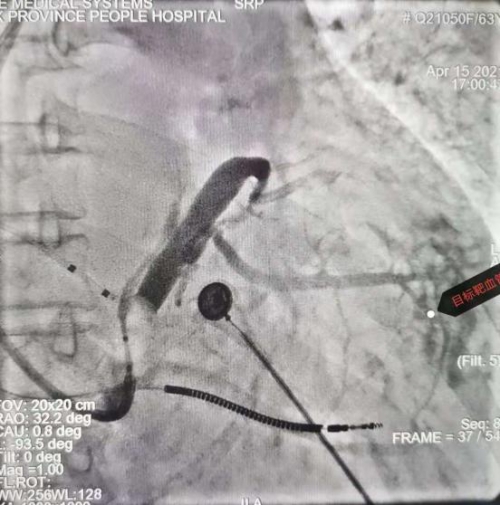

造影显目标靶血管

左室电极到达靶血管部位,测试参数正常